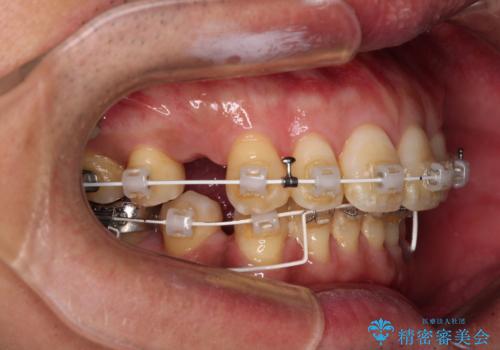

- 審美装置

- 治療期間

- 2年

非常に咬合力が強いため、抜歯したスペースが閉じるのか不安でしたが、順調に歯が移動し、予定よりも早く治療を終えることができました。